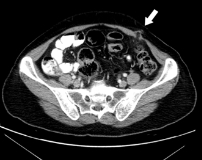

Постановка диагноза троакарной грыжи – задача врача-хирурга. При осмотре обращают внимание на наличие пальпируемого выпячивания, возможность его вправления в брюшную полость, наличие симптома кашлевого толчка, размеры грыжевых ворот. У тучных людей пальпация грыжи затруднена, поэтому отсутствие физикальных признаков не позволяет исключить такой диагноз. Для комплексного обследования пациентов применяются инструментальные методы диагностики:

- Рентгенография ОБП. Исследование с пероральным контрастированием проводят для диагностики содержимого грыжи и оценки проходимости кишечника. Обзорная рентгенография помогает выявить перитонит и другие осложнения. Для верификации диагноза в нестандартных клинических ситуациях используют КТ брюшной полости.